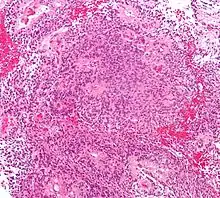

| Micrograph of an ependymoma. H&E stain. | |

Ependymomas are composed of cells with regular, round to oval nuclei. There is a variably dense fibrillary background. Tumor cells may form gland-like round or elongated structures that resemble the embryologic ependymal canal, with long, delicate processes extending into the lumen; more frequently present are perivascular pseudorosettes in which tumor cells are arranged around vessels with an intervening zone consisting of thin ependymal processes directed toward the wall of the vessel.[4]